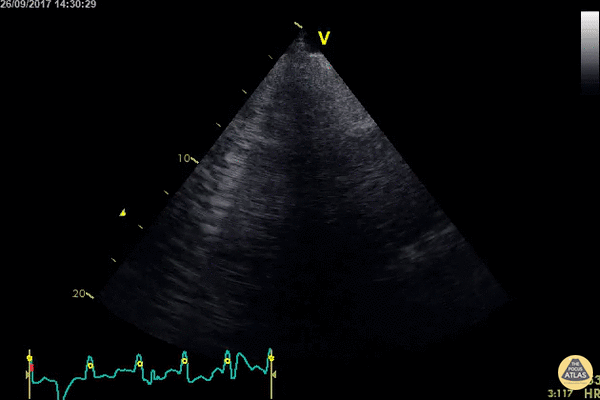

Lung U/S for the case found here:

(U/S source: http://www.thepocusatlas.com/pulmonary/)